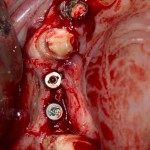

Рекомендации по установке имплантов. Для всех. Часть III